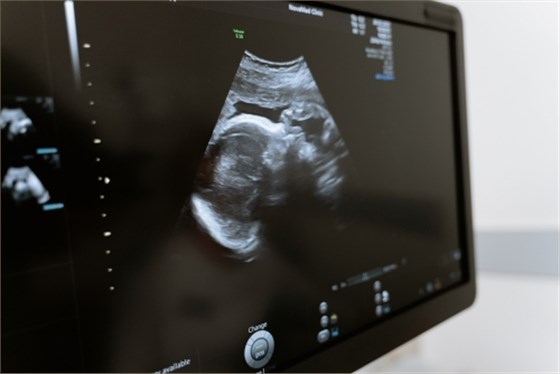

3、盆腔B超檢查:包括雙合診和三合診,可以判斷被檢者子宮、卵巢及盆腔內(nèi)是否存在異常包塊或腫瘤等,多用于診斷子宮肌瘤、卵巢囊腫等疾病;

5、乳腺彩超檢查:乳腺彩超檢查主要以超聲波為基礎(chǔ),可觀察到乳腺內(nèi)是否存在異常包塊,多用于乳腺增生、乳腺纖維瘤及乳腺癌等疾病的篩查。